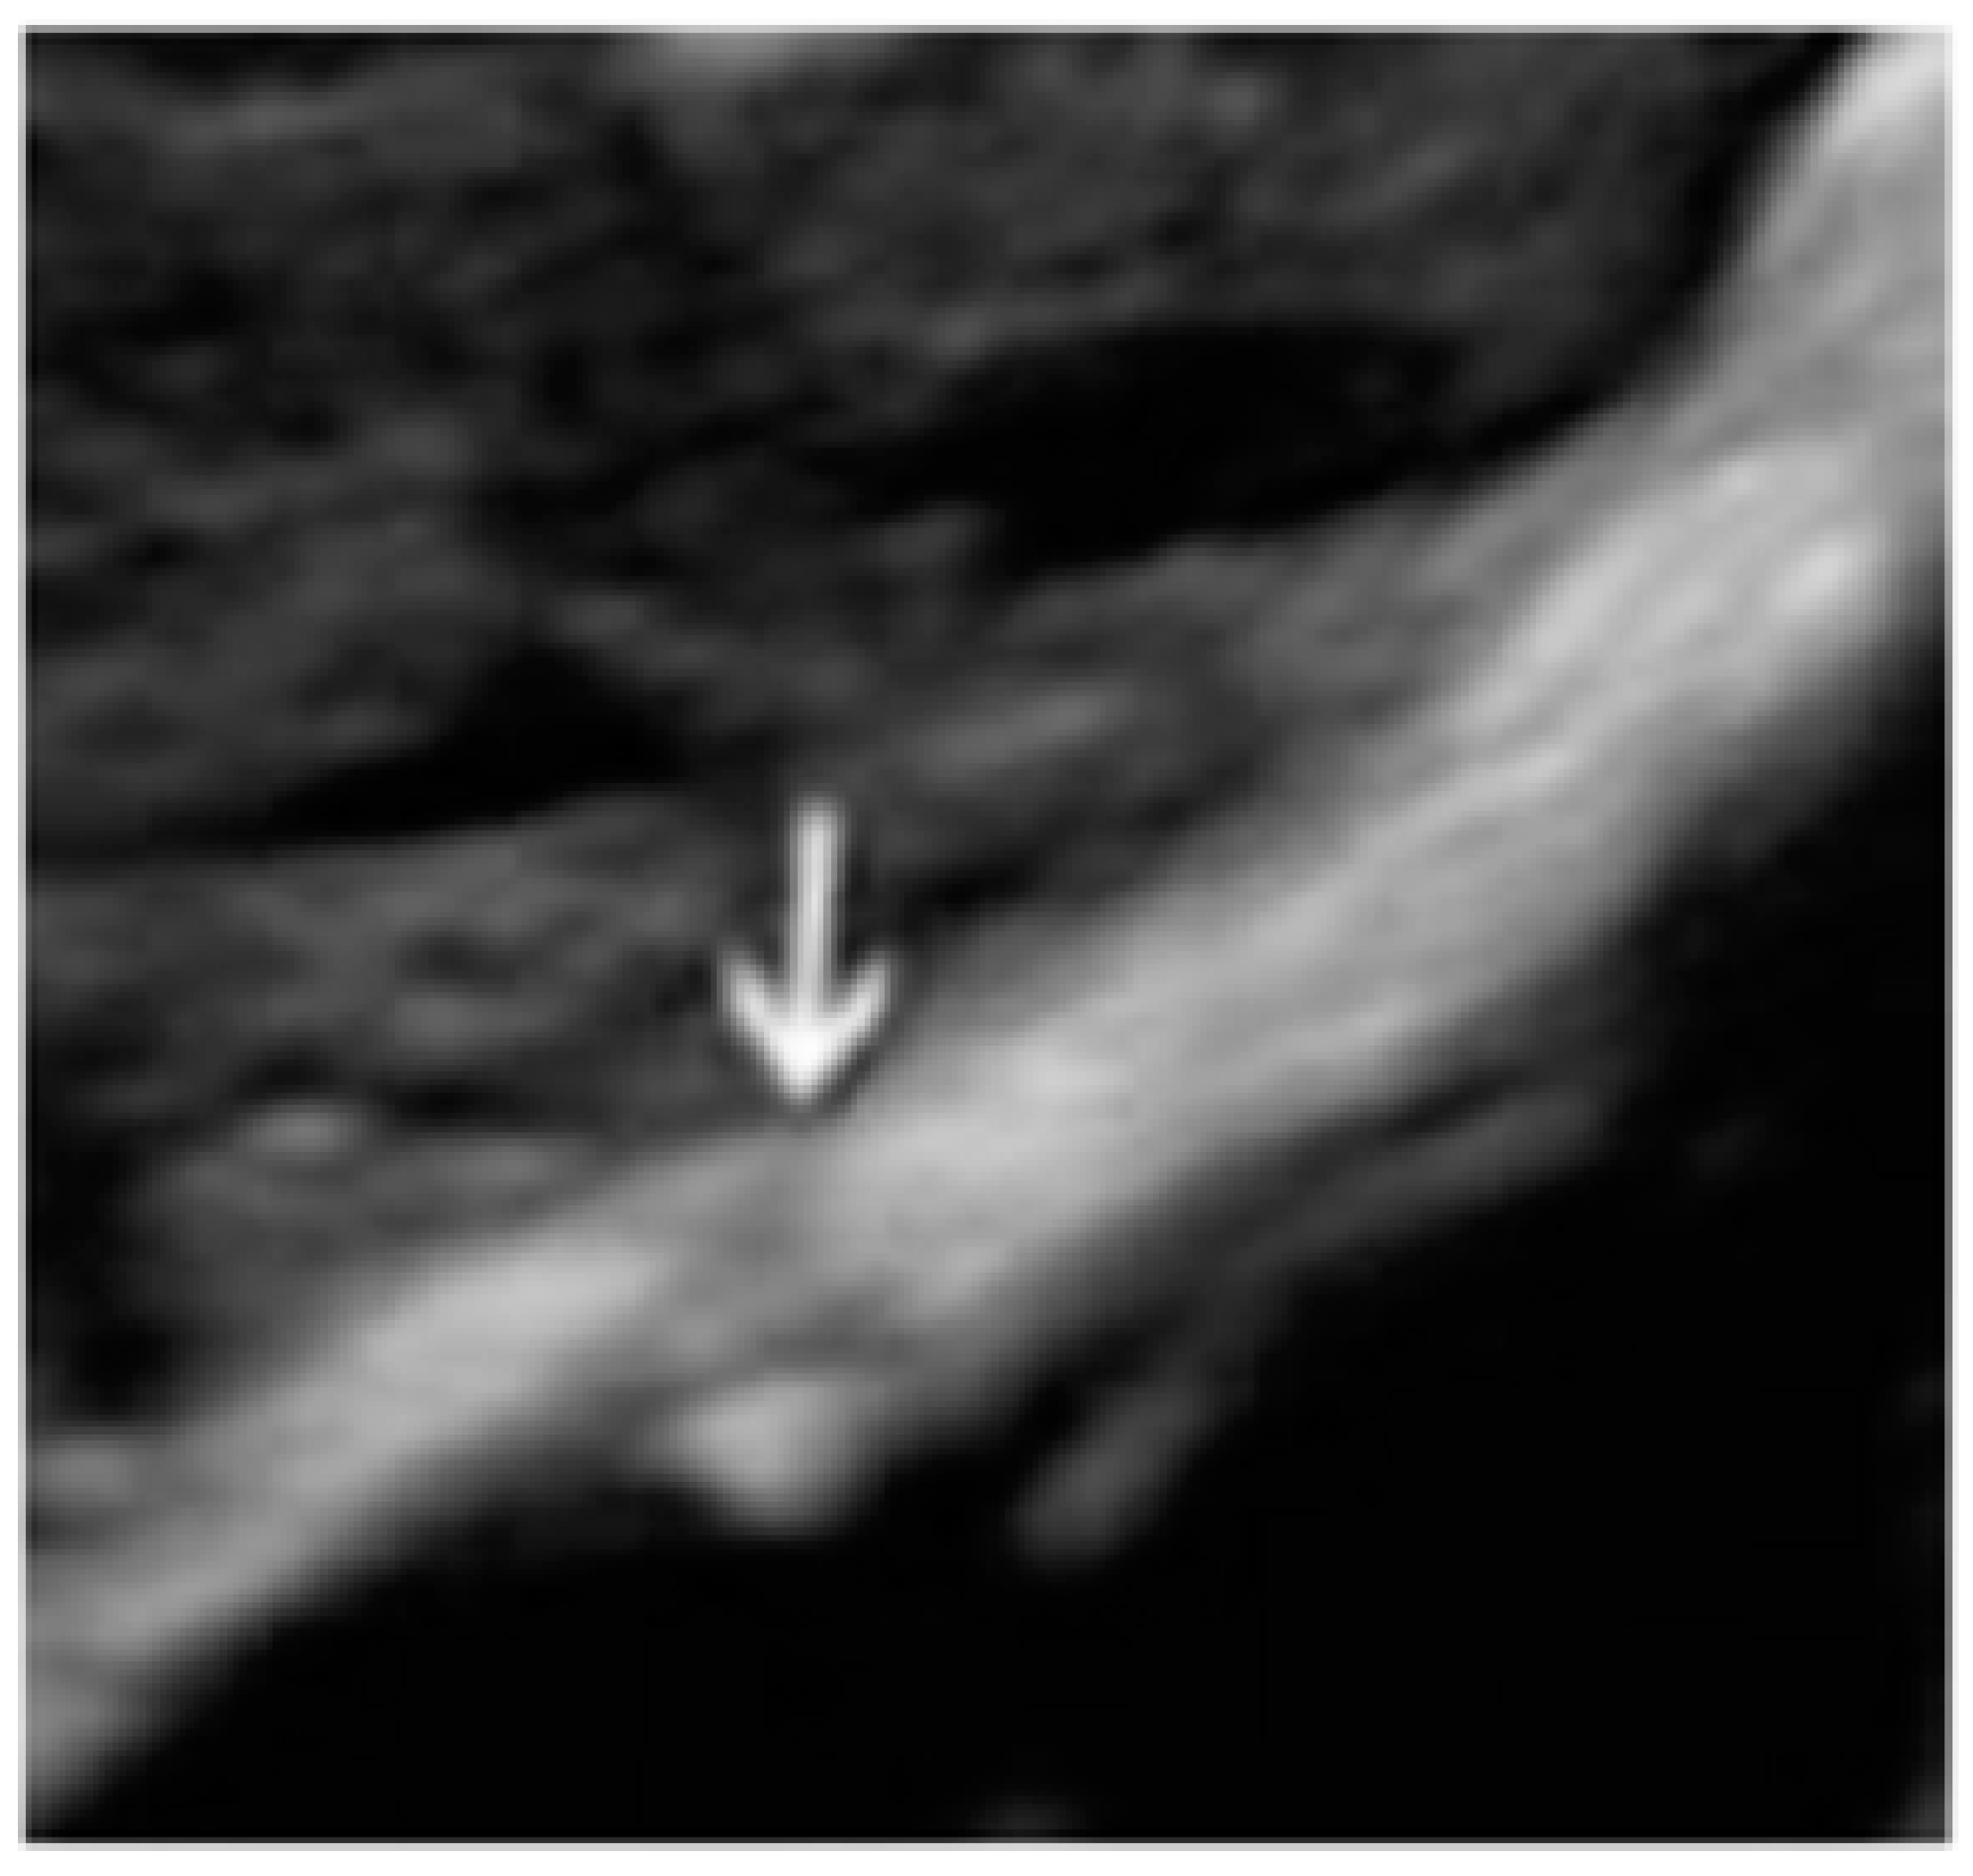

- The presence of hypoechogenic associated tissue (hypoechoic areas surrounding a small cyst area; we called this a “hat”). This tissue does not protrude or invaginate the peritoneal surface.

- The lesion may be convex, protruding from the peritoneal surface into the peritoneal cavity (we called this “bulging”), or it may appear as a concave defect in the peritoneum (we called this a “pocket”).

- The presence of hyperechoic foci (we called this a “pearl”).

- The presence of velamentous (filmy) adhesions associated to the lesion (we called this a “veil”).

3.3. Cystic Lesions Arranged in a Cluster